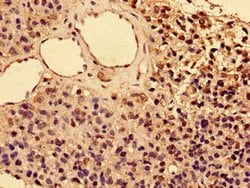

| Anwendungen | Immunohistochemistry (Paraffin), Western Blot, Immunocytochemistry |